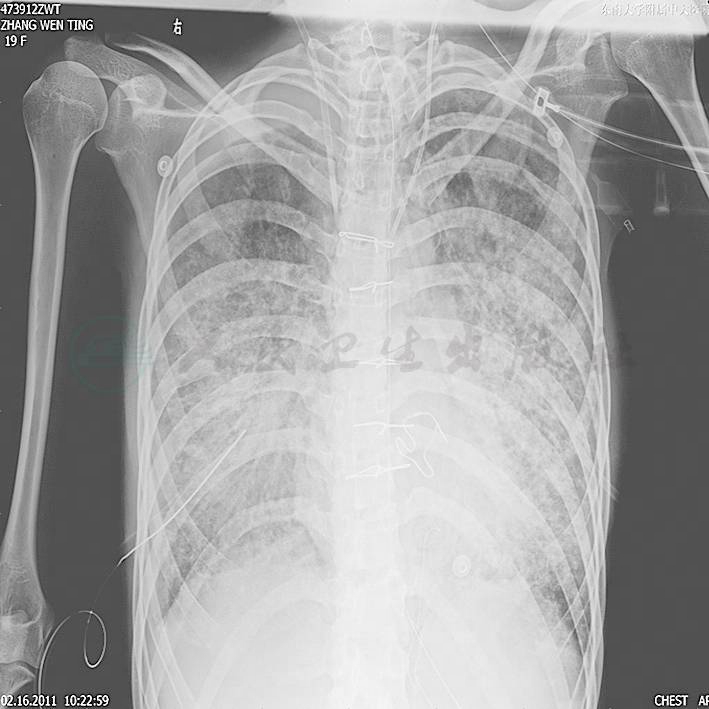

第二阶段(入院后第7~26天):二尖瓣置换术后患者心功能明显改善,多次复查心脏超声均提示心脏舒张及收缩功能未见明显异常,瓣膜功能良好。但患者感染难以控制,考虑感染源:①肺部感染:无法脱离ECMO,胸片提示双肺渗出影(图1),多次痰培养结果均提示鲍曼不动杆菌(MDR);②血源性感染:多次外周血及导管血培养提示洋葱伯克霍尔德菌;③感染性心内膜炎:考虑患者存在急性感染性心内膜炎,瓣膜赘生物形成,多为革兰阳性杆菌感染,但赘生物培养却未见细菌生长。鉴于以上感染相关证据,调整抗感染治疗方案为达托霉素和美罗培南联合左氧氟沙星,并加强气道管理,入院24天后病情明显好转,感染得到控制,逐渐增加呼吸机支持条件,并降低ECMO辅助条件,患者氧合及循环情况均未见恶化,复查胸片渗出较前吸收(图2~图4),故入院后第26天脱离ECMO,在常规机械通气的情况下,患者指脉氧饱和度可维持在95%左右,监测乳酸在1.0mmol/L左右,经皮氧分压88mmHg,经皮二氧化碳分压50mmHg。

图1 开始ECMO胸片